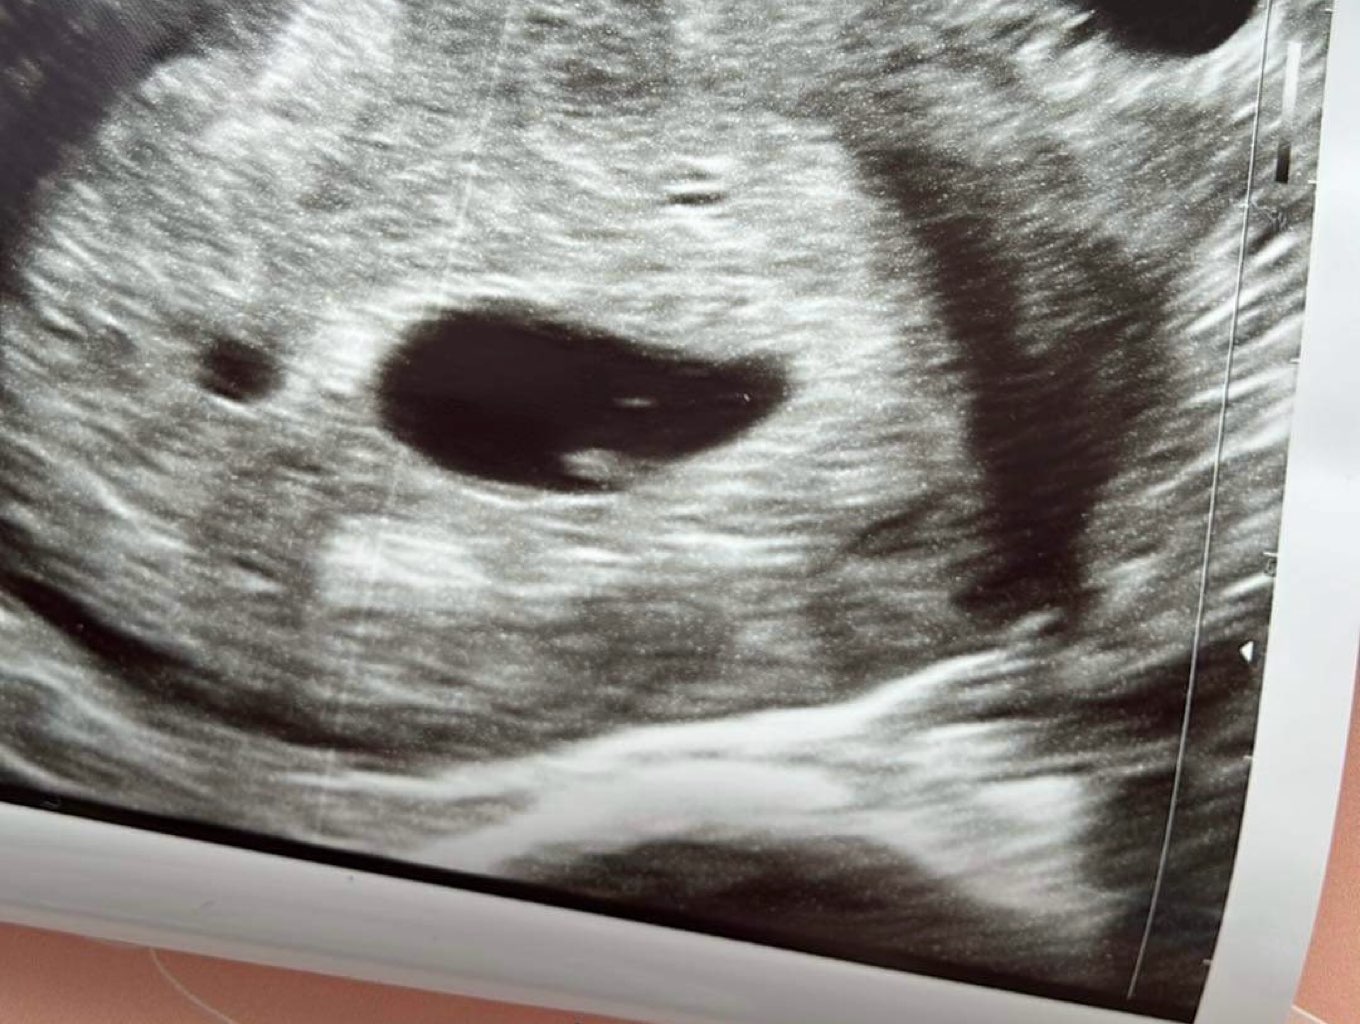

U mnie dziś po wizycie, wiadomo tyle, co nic. Spodziewałam się już bijącego serca, bo powinno być 6+4 około dziś. Na USG końcówka 5, wczesny 6 tydzień. Pęcherzyk w macicy, zarodek jest, ale bez akcji serca. Coś już lekko mrugało, ale lekarz mówiła ze to jeszcze nie to. Kontrola u niej za 3 tyg + mam zlecona już badania, więc zakładam że będzie dobrze.

Trochę czuję przerażenie. Bo to trzecie.. mam nadzieję, ze przejdzie mi i że serduszko pojawi się. Test pozytywny był już 29.01, więc kurczę jakoś liczyłam że już jest czas serduszka, no ale równie dobrze może już być jutro. Na zdjęciu też w zasadzie mikro kropek. Mam nadzieję, że zmierzamy w dobrą stronę..

patrząc po zdjęciu zdjęcia USG chyba ten sprzęt i tego lekarza nie jest jakiś szałowy. Więc może być tak, że serduszko jest tylko nie zauważył ?🤨

ma nowy sprzęt. Dosłownie nowy. 😅 nawet jakoś automatycznie wyliczał wielkość pęcherzyka, a poprzedni co miała to musiała ręcznie zaznaczać obszar